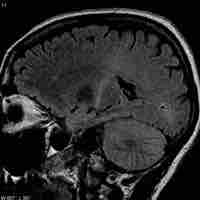

Brain Tumors

A brain tumor is a pathological abnormal growth of cells in the brain.